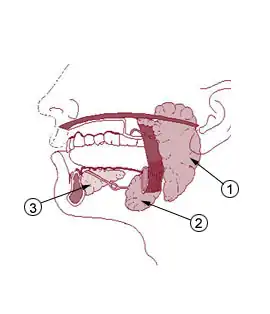

Humans have three major salivary glands: parotid, submandibular, and sublingual. These glands, along with additional minor salivary glands, secrete a rich mixture of biological chemicals, electrolytes, proteins, genetic material, polysaccharides, and other molecules. Most of these substances enter the salivary gland acinus and duct system from the surrounding capillaries via the intervening tissue fluid, although some substances are produced within the glands themselves. The level of each salivary component varies considerably depending on the health status of the individual and the presence of disease (oral or systemic). By measuring these components in the saliva, it is possible to screen for a variety of infections, allergies, hormonal disturbances, and neoplasms.